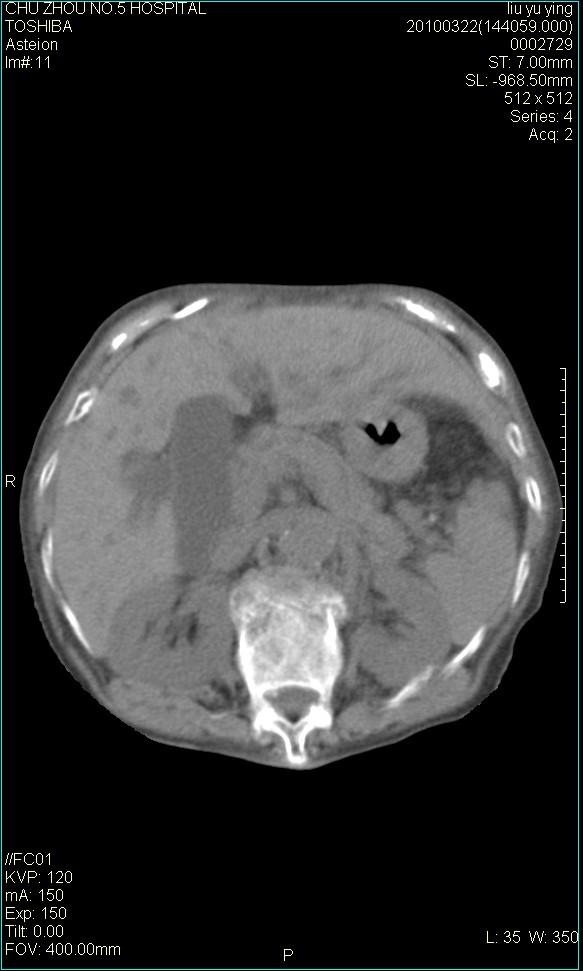

以下是引用科室第一人在2010-3-23 6:50:00的发言:[br]胆总管下段梗阻,多为肿瘤性病变,巨形胆囊,胆囊炎胆囊窝积液。[br]双侧胸腔积液,右降

以下是引用随光逐影在2010-3-23 8:12:00的发言:[br]1)胆系低位梗阻(肝内外胆管扩张,胆囊增大),原因待查。2)胆囊炎。3)双侧少量胸腔积液。4)降主动脉迂曲。